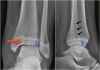

X-ray : 삼면 골절(The triplane fracture)

AP view : Salter-Harris type Ⅲ injury

-

Lateral view : Salter-Harris type Ⅱ injury